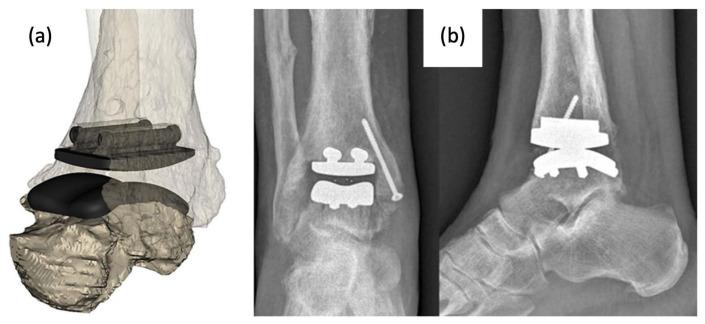

The foot and ankle serve vital roles in weight bearing, balance, and flexibility but are susceptible to many diverse ailments, making treatment difficult. More commonly, Total Ankle Arthroplasty (TAA) and Total Talus Replacement (TTR) are used for patients with ankle degeneration and avascular necrosis of the talus, respectively. Ankle prosthesis and orthosis are also indicated for use with lower limb extremity amputations or locomotor disability, leading to the development of powered exoskeletons. However, patient outcomes remain suboptimal, commonly due to the misfitting of implants to the patient-specific anatomy. Additive manufacturing (AM) is being used to create customized, patient-specific implants and porous implant cages that provide structural support while allowing for increased bony ingrowth and to develop customized, lightweight exoskeletons with multifunctional actuators. AM implants and devices have shown success in preserving stability and mobility of the joint and achieving fast recovery, as well as significant improvements in gait rehabilitation, gait assistance, and strength for patients. This review of the literature highlights various devices and technologies currently used for foot and ankle prosthesis and orthosis with deep insight into improvements from historical technologies, manufacturing methods, and future developments in the biomedical space.

足踝在负重、平衡和灵活性方面起着至关重要的作用,但易患多种不同疾病,这使得治疗变得困难。更常见的是,全踝关节置换术(TAA)和距骨全置换术(TTR)分别用于患有踝关节退变和距骨缺血性坏死的患者。踝关节假体和矫形器也适用于下肢截肢或运动功能障碍的患者,从而推动了动力外骨骼的发展。然而,患者的治疗效果仍然不尽人意,这通常是由于植入物与患者特定解剖结构不匹配所致。增材制造(AM)正被用于制造定制的、针对患者的植入物和多孔植入物笼,这些植入物和笼子在提供结构支撑的同时,还能促进骨长入增加,并开发具有多功能致动器的定制轻质外骨骼。增材制造的植入物和设备在保持关节稳定性和活动能力以及实现快速康复方面已取得成功,同时在患者的步态康复、步态辅助和力量方面也有显著改善。这篇文献综述重点介绍了目前用于足踝假体和矫形器的各种设备和技术,并深入洞察了从历史技术、制造方法到生物医学领域未来发展的改进情况。